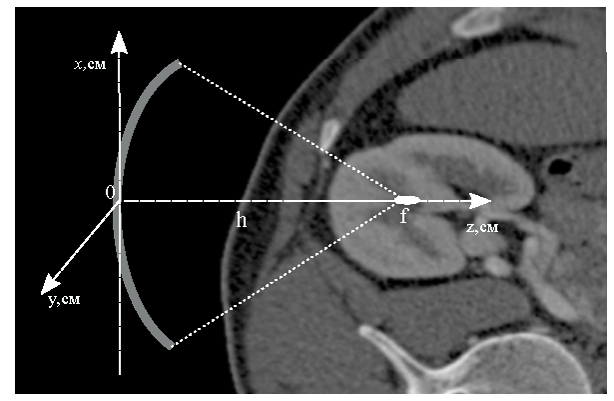

Students of LIMU Katya Ponomarchuk and Nastya Bobina received student stipends from Focused Ultrasound Global Internship Program for summer 2018. Katya’s project is devoted to histological and ultrastructural analysis (EM) of lesions induced by high intensity focused ultrasound in hematoma using boiling histotripsy method. Nastya proposed a project on modeling focused ultrasound beams in inhomogeneous biological tissue using data of computed tomography (CT). Congratulations to Nastya and Katya!